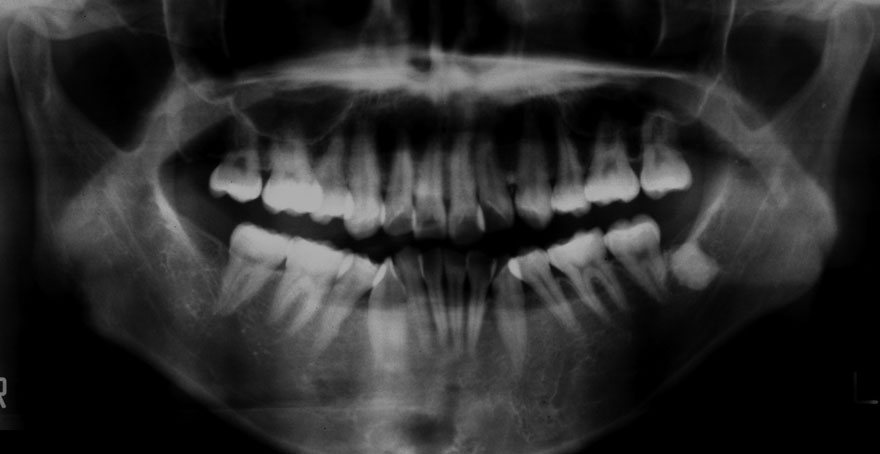

←母親 30歳時のレントゲン写真